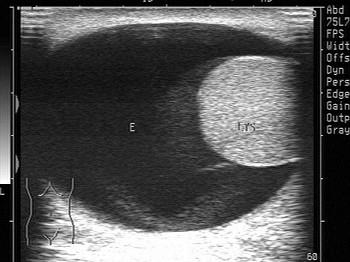

问题 鞘膜积液分四种,如图所示为哪种?(?)

选项 A.睾丸鞘膜积液 B.精索鞘膜积液 C.睾丸精索鞘膜积液 D.交通性鞘膜积液 E.以上都不是

答案 A